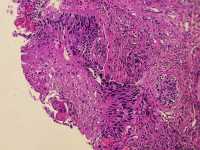

女39岁宫颈活检HPV53HPV58阳性 CIN2?

免疫组化分别是P16 Ki67

考虑为CIN2累腺

HSIL累腺。